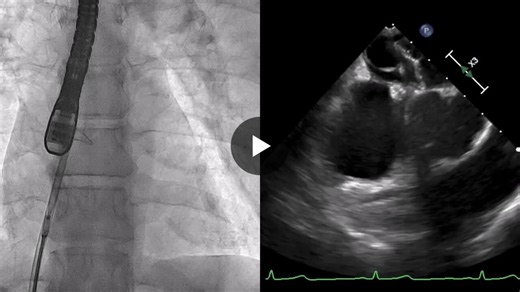

Echo - PFO vs ASD

2:10

PFO Closure Procedure - Scott Li…